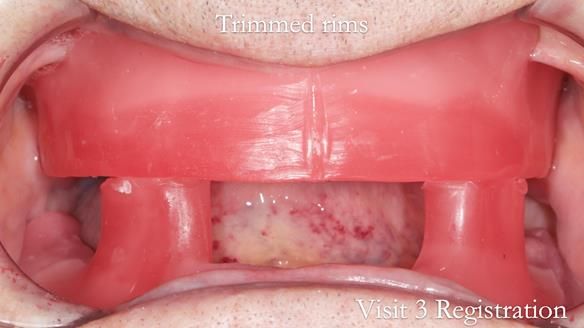

The clinical situation and treatment process is shown in detail below with photographs. I (Finlay Sutton) provided the clinical work and Rowan Garstang provided the technical work.